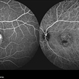

- Fundus autofluorescence imaging of a patient with autosomal recessive Best disease